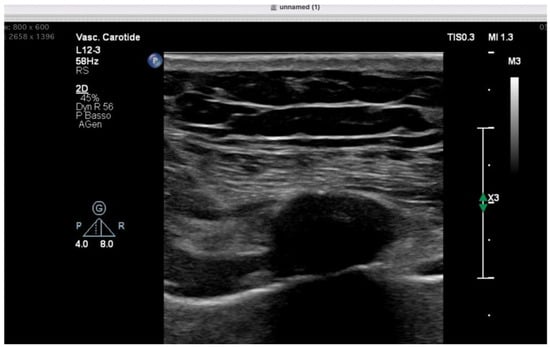

Anesthetic Management of Eosinophilic Granulomatosis with Polyangiitis: A Narrative Review with an Illustrative Case in Cardiac Surgery

by Debora Emanuela Torre and Carmelo Pirri

Background: Eosinophilic granulomatosis with polyangiitis (EGPA), formerly Churg–Strauss syndrome, is a rare necrotizing vasculitis characterized by asthma, eosinophilia, and systemic granulomatosis vasculitis. Perioperative risk is primarily driven by airway hyperreactivity, potential cardiac disease, chronic immunosuppressive therapy, and reported alterations in plasma cholinesterase [...] Read more.

Background: Eosinophilic granulomatosis with polyangiitis (EGPA), formerly Churg–Strauss syndrome, is a rare necrotizing vasculitis characterized by asthma, eosinophilia, and systemic granulomatosis vasculitis. Perioperative risk is primarily driven by airway hyperreactivity, potential cardiac disease, chronic immunosuppressive therapy, and reported alterations in plasma cholinesterase activity. Evidence specifically addressing anesthetic management remains scarce and largely limited to case-based reports. Methods: A focused narrative review was conducted by searching MEDLINE (via PubMed), Scopus, and Embase from inception to January 2026 for publications reporting perioperative anesthetic management in patients with EGPA/Churg–Strauss syndrome. Case reports and case-based descriptions providing explicit anesthetic details were qualitatively synthesized. Results: Available evidence consists predominantly of isolated case reports across heterogeneous surgical settings, including ENT, abdominal, orthopedic, ambulatory, pediatric, and rare cardiac procedures. Recurring perioperative principles include optimization of bronchial disease and continuation of inhaled therapy; minimization of airway stimulation and avoidance of histamine-releasing drugs; selection of induction agents preserving hemodynamic stability in the presence of myocardial involvement; preference for non-depolarizing neuromuscular blockade with quantitative monitoring (and consideration for sugammadex when appropriate); individualized corticosteroid management and multimodal, opioid-sparing analgesia, often supported by regional techniques. Conclusions: In the absence of dedicated perioperative guidelines, anesthetic care for EGPA should be individualized based on clinical phenotype and organ involvement. A structured approach targeting airway protection, cardiovascular stability, safe neuromuscular management, and opioid-sparing analgesia may represent a pragmatic risk-mitigation framework. These considerations are illustrated by an institutional experience in mitral valve surgery. Full article

Show Figures

Figure 1